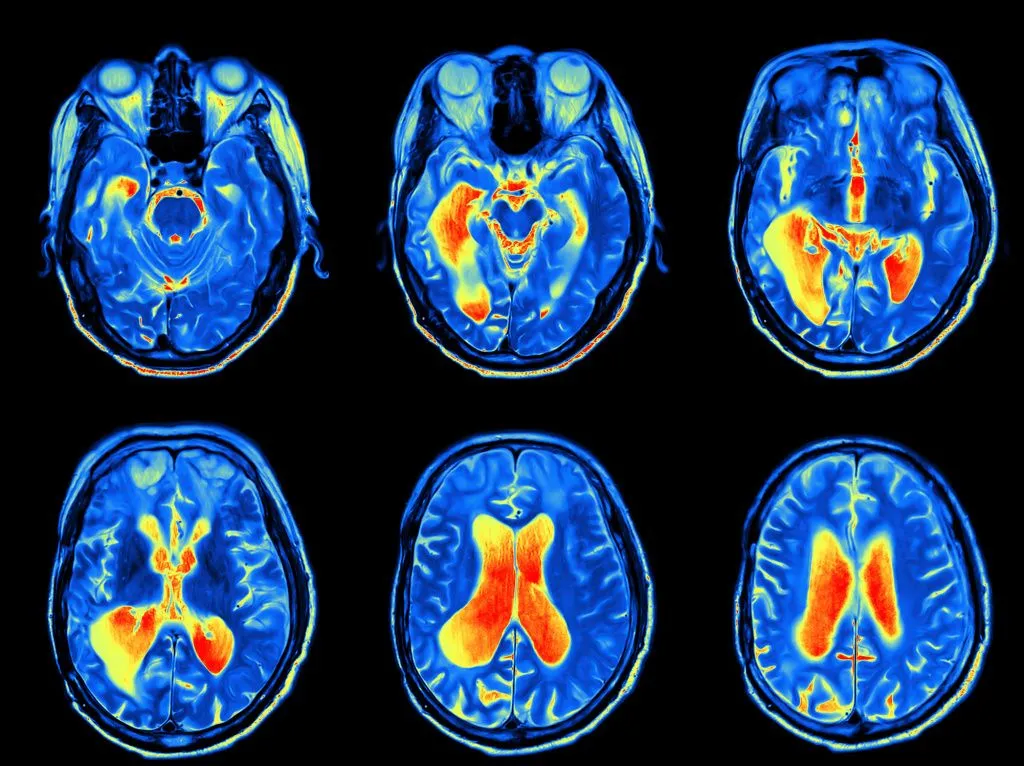

2. НСйровизуализация (МРВ, ПЭВ). Π‘ΠΊΠ°Π½ΠΈΡ€ΠΎΠ²Π°Π½ΠΈΠ΅ ΠΌΠΎΠ·Π³Π° ΠΌΠΎΠΆΠ΅Ρ‚ Π²Ρ‹ΡΠ²ΠΈΡ‚ΡŒ структурныС ΠΈΠ»ΠΈ Ρ„ΡƒΠ½ΠΊΡ†ΠΈΠΎΠ½Π°Π»ΡŒΠ½Ρ‹Π΅ измСнСния Π² ΠΎΠΏΡ€Π΅Π΄Π΅Π»Ρ‘Π½Π½Ρ‹Ρ… Π·ΠΎΠ½Π°Ρ… (Π½Π°ΠΏΡ€ΠΈΠΌΠ΅Ρ€, Π² Π³ΠΈΠΏΠΏΠΎΠΊΠ°ΠΌΠΏΠ΅ ΠΏΡ€ΠΈ дСпрСссии ΠΈΠ»ΠΈ Π² ΠΏΡ€Π΅Ρ„Ρ€ΠΎΠ½Ρ‚Π°Π»ΡŒΠ½ΠΎΠΉ ΠΊΠΎΡ€Π΅ ΠΏΡ€ΠΈ Π‘Π”Π’Π“). ΠšΠ°Ρ€Ρ‚ΠΈΠ½ΠΊΠ° становится ΠΎΠ±ΡŠΠ΅ΠΊΡ‚ΠΈΠ²Π½Ρ‹ΠΌ Π΄ΠΎΠΊΠ°Π·Π°Ρ‚Π΅Π»ΡŒΡΡ‚Π²ΠΎΠΌ.